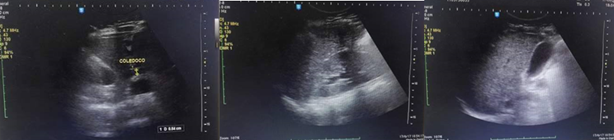

Figura 1. Ecografía de Abdomen

Reporte

Hígado de ecogenicidad heterogénea, por infiltración adiposa difusa, moderada, bordes irregulares, sin otras lesiones intrahepáticas ocupantes de espacio, visibles por este método de estudio, liquido libre perihepático y espacio de Morrison.

Vesícula biliar de paredes delgadas, alitiásicas, sin signos inflamatorios francos.

Páncreas no visibles por interpretación de gas.

Lo valorable de las vías biliares intra y extrahepáticas de calibre normal. Signos de esplenomegalia y liquido libre en espacio peri-esplénico.

Conclusión: Hallazgos a correlación con Cirrosis Hepática.